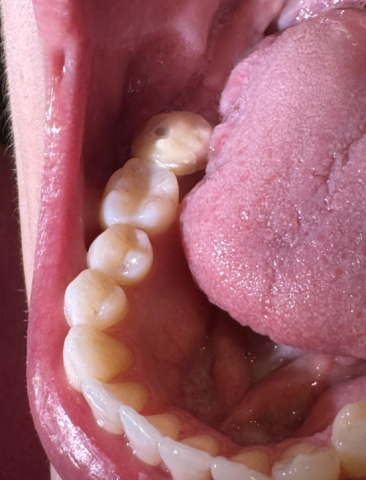

Image Observations: The picture shows the lower right side of the mouth (Mandibular quadrant).

The tooth farthest back (most posterior) appears to have a restoration (filling or inlay/onlay) or possibly a crown which exhibits a large, dark, and deep-looking defect or void on its biting surface (occlusal surface). The defect appears dark brown/black with a distinct border.

The adjacent tooth (second molar/premolar) also shows signs of an existing white or tooth-colored filling (composite or glass ionomer) with some possible discoloration or breakdown at the margins.

The surrounding soft tissues (gums and tongue) appear generally healthy.

Client Statement: "Does my crown implant look normal?"

Clarification: It is most likely that the question refers to a crown placed on a natural tooth, or a restoration on a natural tooth. A dental implant would typically have a crown cemented on an abutment, and the visible issue appears to be within the structure of the tooth/crown itself.

The primary concern is the large, dark defect on the most posterior tooth.

| 1. Secondary Caries (Decay) | The most likely diagnosis. Decay has formed around or under the existing restoration (crown/filling) due to marginal leakage. The dark color is staining combined with the decaying dentin. The defect appears very deep, possibly nearing the pulp chamber (nerve). | High Risk. If this is active decay, it will rapidly reach the pulp (nerve), especially within a 14-day timeframe or less given its depth. This progression leads to pulpitis, which can be irreversible and cause severe pain, abscess formation, and require Root Canal Treatment or Extraction. |

| 2. Failed/Fractured Restoration | The restoration itself (filling or crown material) has fractured, leaving a deep hole that is now stained with food and plaque. | Moderate Risk. While the material is fractured, the exposed tooth structure is highly vulnerable to rapid decay (Secondary Caries - see #1) and sensitivity. |

| 3. Arrested Stain/Pigmentation | Highly unlikely given the size and depth. This would be a stable, deep stain or a dark-colored restorative material (like silver amalgam) that has fractured. | Low Risk. Only if the material is stable. If it's a fractured filling (Amalgam), it must be replaced to prevent decay. |

Time Frame to Scale Up: Given the apparent depth of the defect, the condition could escalate from asymptomatic or mild sensitivity to a severe, painful pulp infection (requiring root canal) within 14 days.

The defect on the posterior tooth is not normal and appears to be a severe case of decay or restoration failure. Immediate consultation is strongly advised.